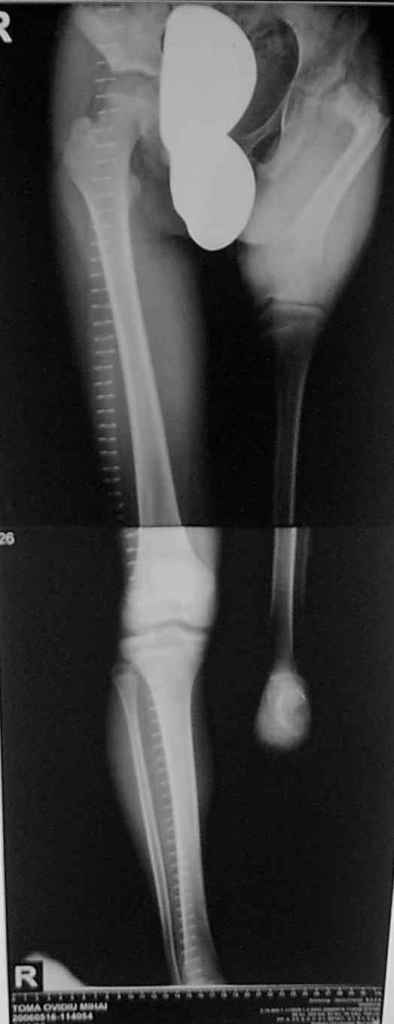

Недостаточно информации для размышлений о тактике лечения, нужны рентгенограммы дистальной части конечности, описание функциональной состоятельности конечности. Удлинение сегмента на такую величину, при таком тазобедренном суставе даже этапно - весьма сомнительная задача. Большие укорочения являются показанием к функциональному протезированию. Думаю, что эту проблему надо решать совместно с протезистами.

Вы имеете дело с Congenital Femoral Deficiency Type 1b or type 2.

Снимки, присланные Вами недостаточны для решения вопроса о тактике лечения - она зависит от того есть или нет псевдоартроза, если есть мобильна ли головка бедра или нет.

Извините за задержку(по техническим обстоятельствам) еще просим извинения за ошибки (трудный перевод). Больной с врожденной гипоплазией проксимальной части бедра, с ацетабулярной дисплазией. В 6 лет первая операция по стабилизации тазобедренного сустава прилагаю Рг. К нам обратился в следующей ситуацией:укорочение на 26см нижней конечности, соха flecta - 45 °.подвижной до 100°, genu flexum 25-30° мобильный до 90°. Активность мышц бедра- очень слабое, мышцы голени и сама голень отстающей в развитии. В настоящее время пациент ходит самостоятельно с протезом. Спасибо всем еще раз за присланные варианты лечения.Rx при рождении:ниже

Rx на сегодняшнии день